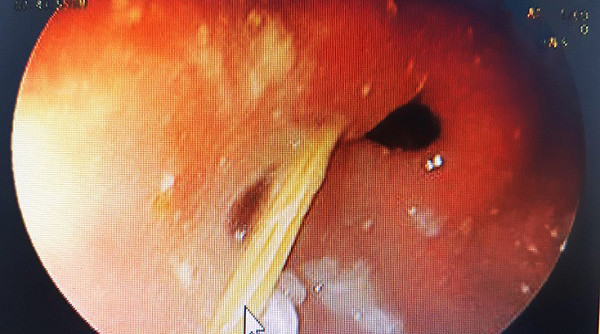

| Hình ảnh chiếc tăm nhọn trong dạ dày bệnh nhân. |